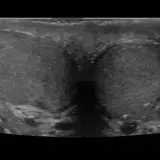

Over 2,100 interactive radiology cases, curated by radiologists for your level of training. Scroll, window, and view cases full screen — just like on PACS. Click linked findings in each writeup to jump straight to them on the image. Cases include sample reports, a focused discussion section, original illustrations, and videos.

完全交互式病例,配备您在 PACS 上期待的各项工具——滚动、调窗、缩放、平移、测量、ROI 和全屏模式。

丰富的标注直接在病例图像上突出关键发现。点击病例讲解中的关联发现,即可跳转至其在扫描上的精确位置。

像在工作站 PAC 上一样滚动、平移、调窗和缩放